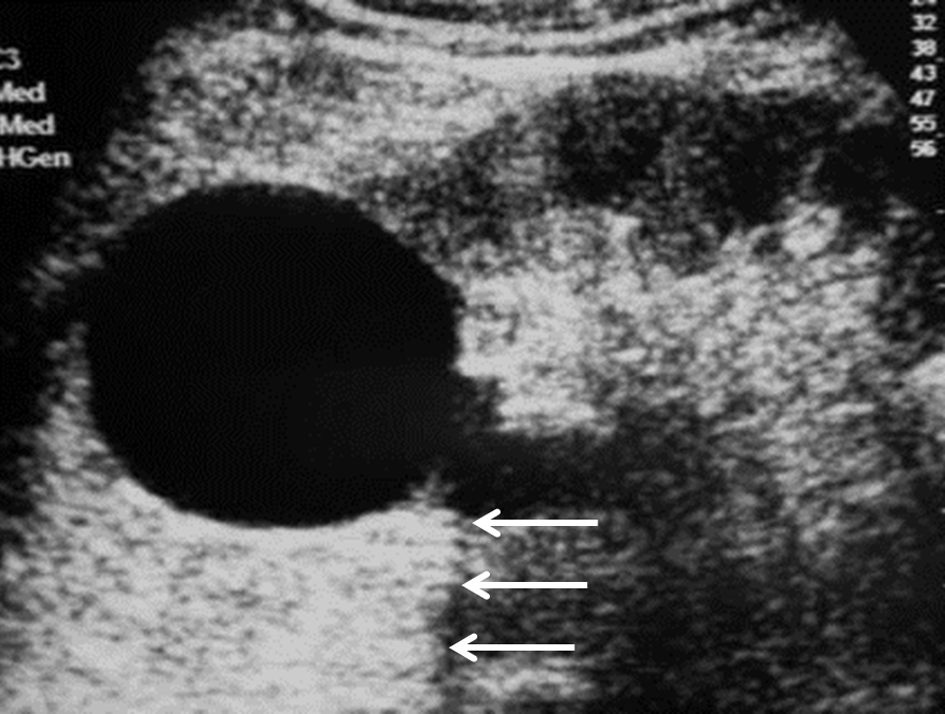

- anéchogène homogène avec renforcement postérieur des échos à l’échographie (figure 31.1) ;

Fig. 31.1 Échographie d’un kyste rénal simple.

Kyste rénal polaire supérieur du rein gauche : masse liquidienne anéchogène sans paroi visible, avec renforcement postérieur (flèches).

Source : CERF, CNEBMN, 2022.